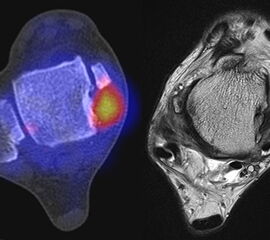

Abbildung 1.8.a und b: Akute Arthritis bei bekannter Gicht in beiden OSG: links die Früh-/Weichteilphase; rechts die Mineralisations­phase. Deutliche, entzündlich bedingte Mehranreicherungen in der Früh-/Weichteilphase. In der Mineralisation­sphase erkennt man die entzündliche Mitreaktion der subchondralen Gelenkabschnitte.

Abbildung 1.8.c - e: Akute Arthritis in beiden OSG, rechts > links. Im SPECT/CT erkennt man die Mitreaktion der subchondralen Gelenkabschnitte. Die Arthritis ist so akut, dass (noch) keine ossären morphologischen Veränderungen im CT abgrenzbar sind.